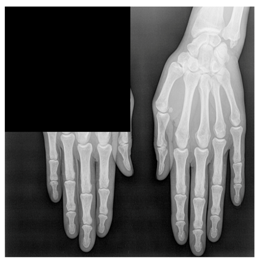

3.2. Separation of the Medical Image

The proposed method is based on the separation of the medical image into two regions: the anatomical region and the black background region. The separation can be done automatically by using an algorithm [4] or manually by using a rectangle to form the ROI [15,19]. In our method, we have used an automatic separation based on a threshold. The threshold was determined starting from the theoretical value 0 corresponding to the black pixel and iteratively increasing it by 1 until reaching a value making it possible to obtain a good separation between the anatomical region (ROI) and the black background region (RONI) for the images of the medical images database. A gray value greater than the threshold belongs to the anatomical object, and a gray value below or equal to the threshold belongs to the black background region of the image. Figure 2 shows an example of the anatomical region and the black background region separation.

Figure 2.

(a) the original image, (b) the anatomical region IAntomical, (c) the black background region IBlackbackground and (d) original image with separation between IAntomical and IBlackbackground.